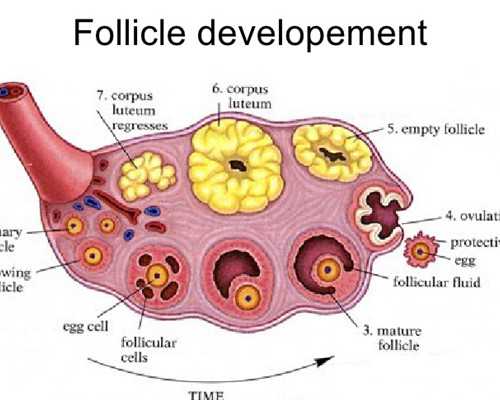

| 2 | 促排卵藥物和b超監測費用 | 不同的促排卵方案藥物種類不同,卵巢儲備功能和機體對藥物的敏感性也有所不同,而這使得每個患者的藥物種類和劑量也不同,因此費用也不同,所以,如果有試管指征,盡早在合適的年齡選擇試管嬰兒治療也是省錢的策略,約5000-13000元左右 |